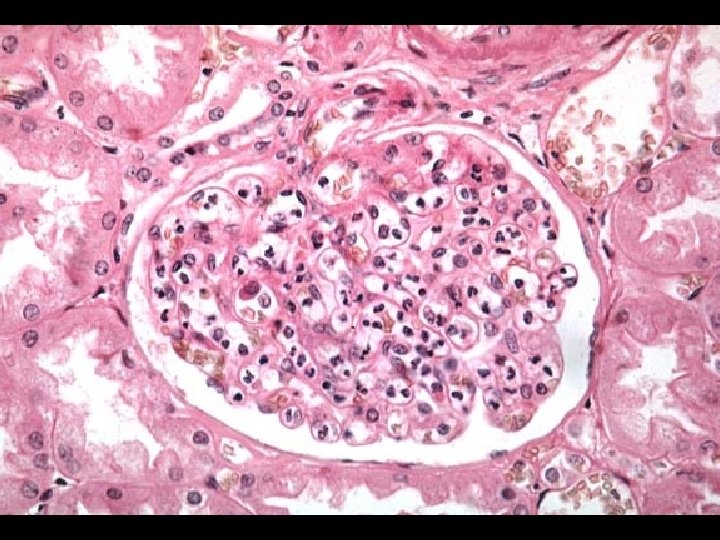

POST-STREPTOCOCCAL ACUTE GLOMERULONEPHRITIS (PSAGN) * Non-suppurative sequelae following pharyngitis and skin infections by Group A Streptococcus (GAS) * 1 to 3 weeks following pharyngitis and skin infections * Characterized by • Edema (peri-orbital) • Hematuria • Hypertension * Male to female ratio of 2: 1

POST-STREPTOCOCCAL ACUTE GLOMERULONEPHRITIS (PSAGN) * Highest incidence/prevalence between 4 to 12 years * Antigens from "Nephritogenic strains“ * M 2, M 12, M 49, M 57, M 59, M 60 * Effector mechanism • Deposition of soluble immune complexes in glomeruli * Laboratory diagnosis • Anti-streptolysin O (ASO) [skin infections show poor response] • Anti-DNase. B • C 3

SYSTEMIC LUPUS ERYTHEMATOSUS (SLE) * Effector mechanisms • Autoantibodies to many autoantigens • Most common autoantibody is to ds-DNA • Immune complex deposition on basement membranes with complement activation and inflammation * Laboratory diagnosis • Anti-nuclear antibody (ANA) • IFA (indirect fluorescent antibody) assay using HEp-2 cells • Homogeneous pattern and titer > 1: 160 • Anti ds-DNA • IFA assay using Crithidia lucilliae • C 3 level